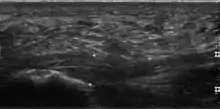

Plantar fasciitis is usually diagnosed by a health care provider after consideration of a person's presenting history, risk factors, and clinical examination.[4][17][18] Palpation along the inner aspect of the heel bone on the sole may elicit tenderness during the physical examination.[4][11] The foot may have limited dorsiflexion due to excessive tightness of the calf muscles or the Achilles tendon.[7] Dorsiflexion of the foot may elicit the pain due to stretching of the plantar fascia with this motion.[4][12] Diagnostic imaging studies are not usually needed to diagnose plantar fasciitis.[7] Occasionally, a physician may decide imaging studies (such as X-rays, diagnostic ultrasound, or MRI) are warranted to rule out serious causes of foot pain.

The plantar fascia has three fascicles-the central fascicle being the thickest at 4 mm, the lateral fascicle at 2 mm, and the medial less than a millimeter thick.[19] In theory, plantar fasciitis becomes more likely as the plantar fascia's thickness at the calcaneal insertion increases. A thickness of more than 4.5 mm ultrasound and 4 mm on MRI are useful for diagnosis.[20] Other imaging findings, such as thickening of the plantar aponeurosis, are nonspecific and have limited usefulness in diagnosing plantar fasciitis.[13]